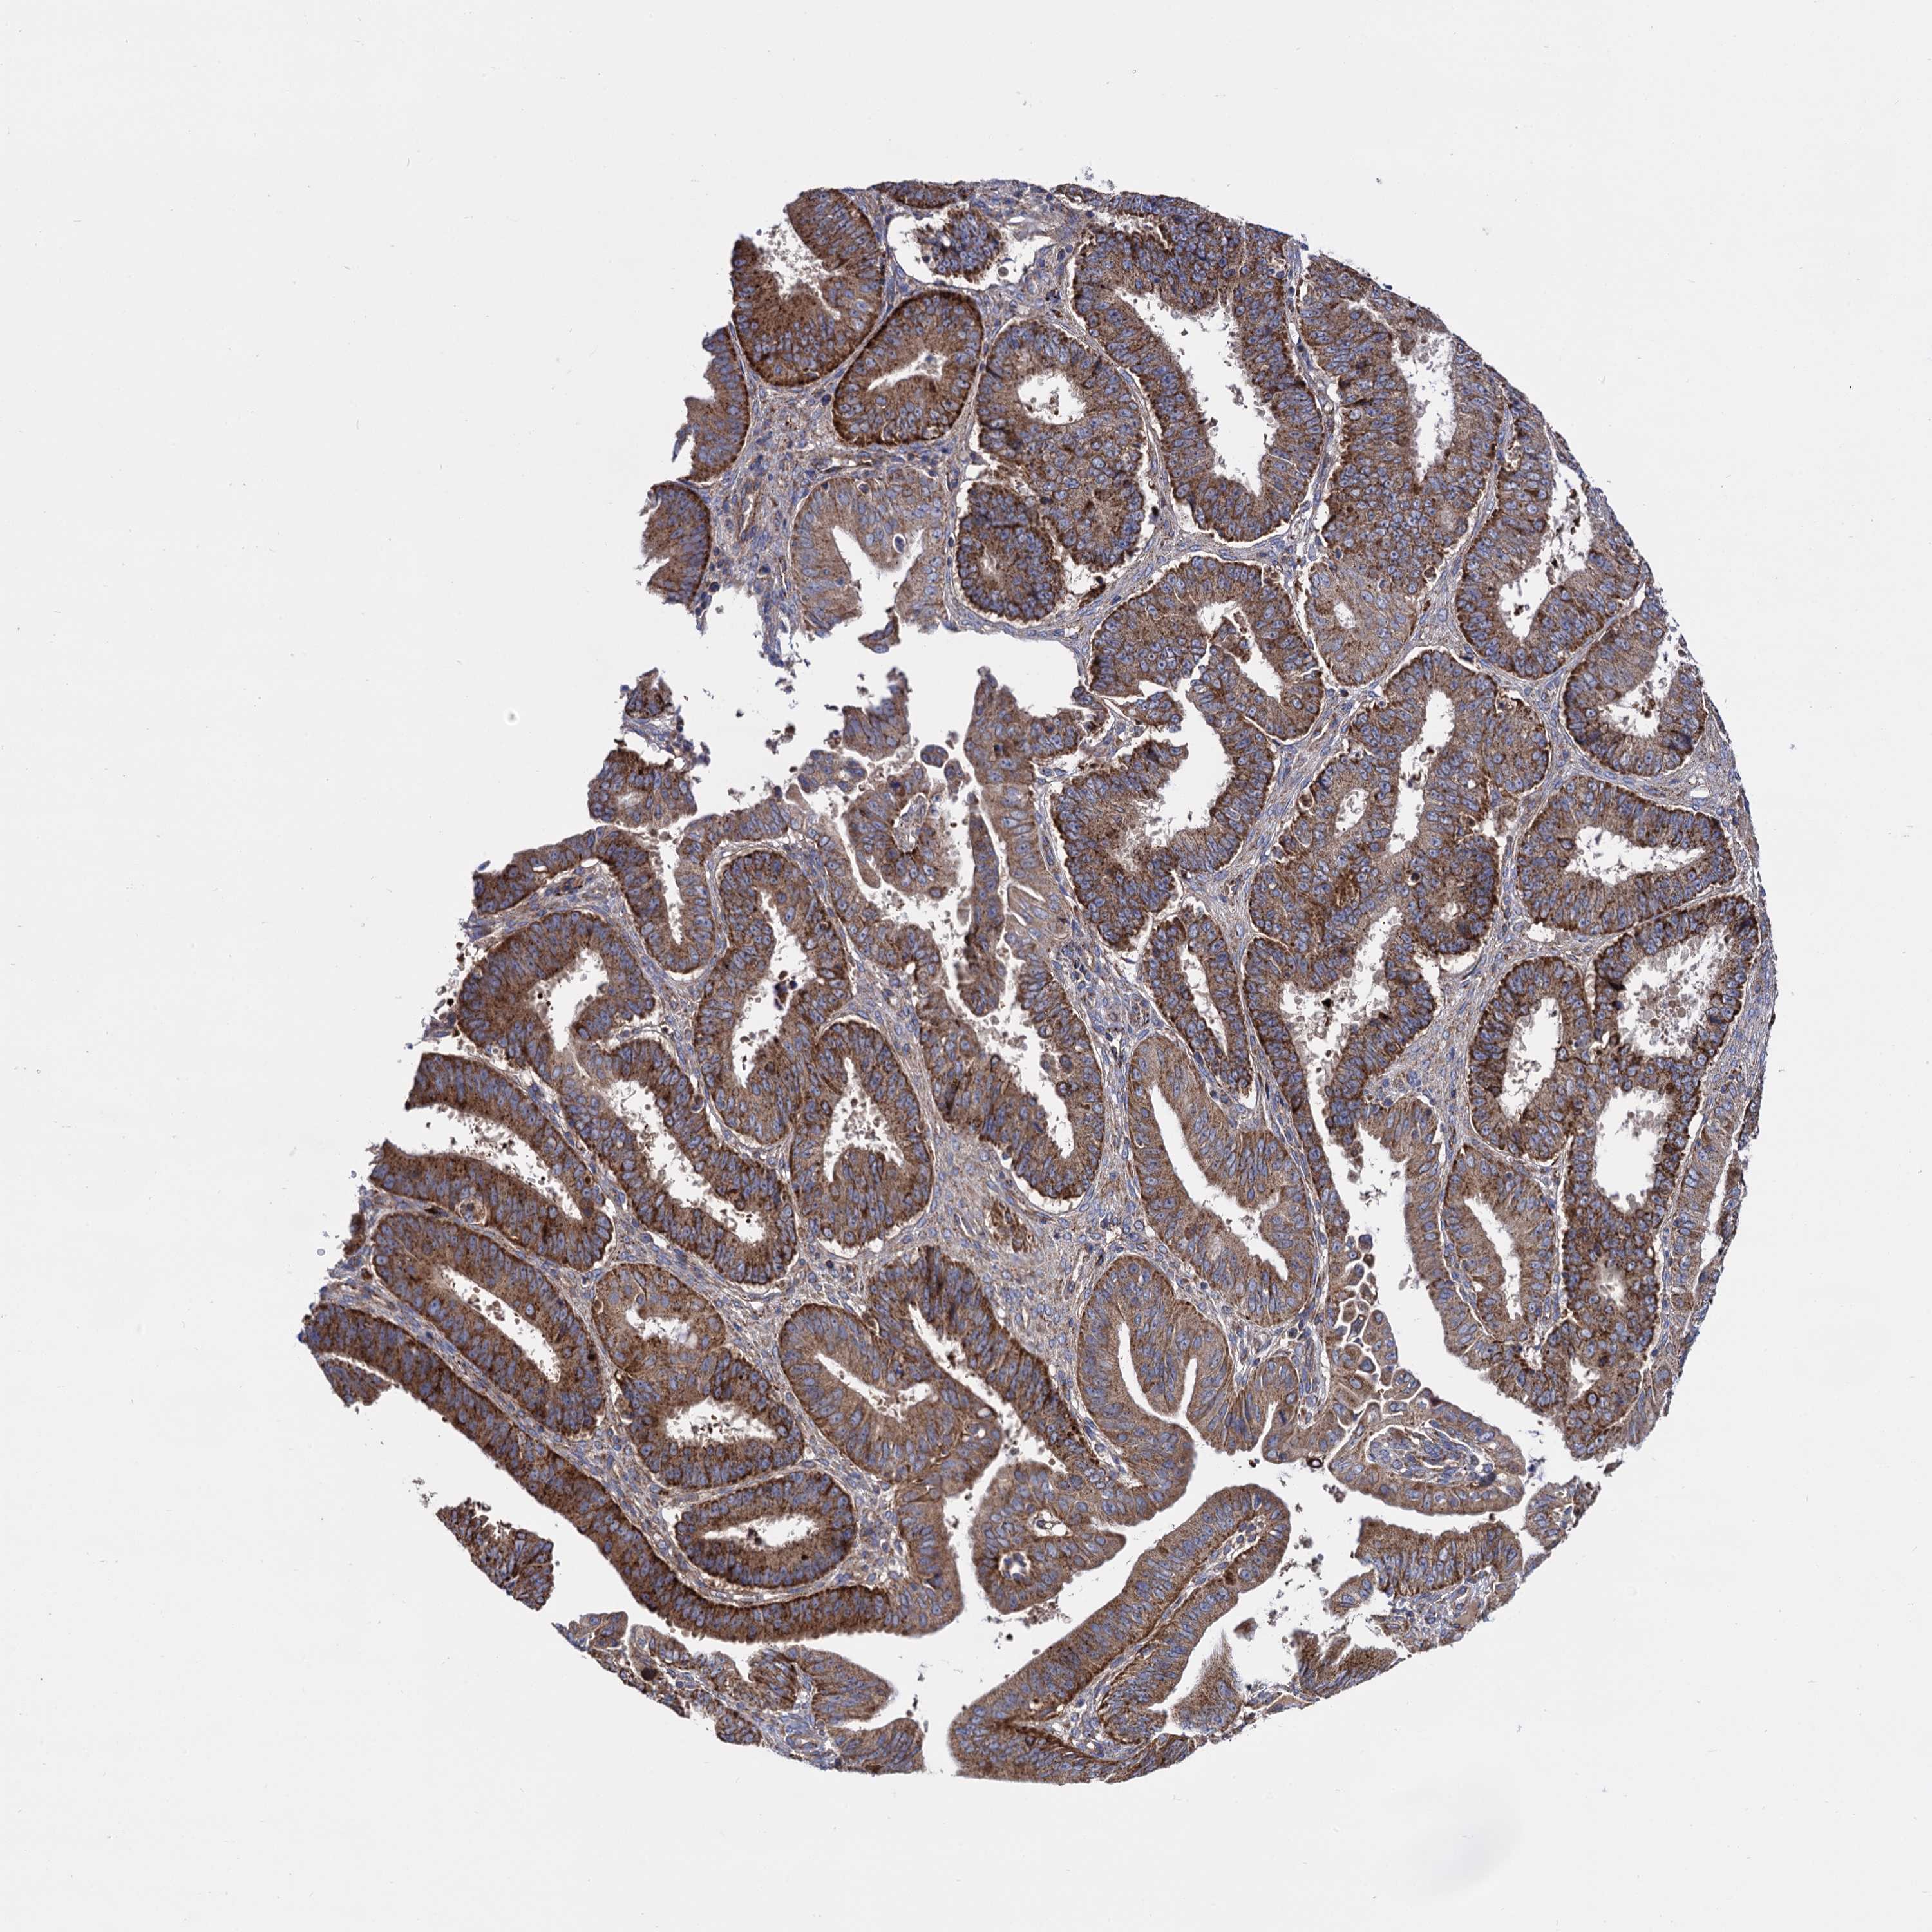

OVARIAN CANCER - Protein expressioni

A mouse-over function shows sample information and annotation data. Click on an image to view it in a full screen mode. Samples can be filtered based on level of antibody staining by selecting one or several of the following categories: high, medium, low and not detected. The assay and annotation is described here.

Note that samples used for immunohistochemistry by the Human Protein Atlas do not correspond to samples in the TCGA dataset.

Antibody stainingi

Antibody staining in the annotated cell types in the current human tissue is reported as not detected, low, medium, or high, based on conventional immunohistochemistry profiling in selected tissues. This score is based on the combination of the staining intensity and fraction of stained cells.

Each image is clickable and will lead to virtual microscopy that enables deeper exploration of all samples and also displays staining intensity scores, fraction scores and subcellular localization as well as patient and tissue information for each sample.

Antibody HPA040845

Staining

High

Medium

Low

Not detected

Intensity

Strong

Moderate

Weak

Negative

Quantity

>75%

75%-25%

<25%

None

Location

Nuclear

Cytoplasmic/membranous

Cytoplasmic/membranous,nuclear

Cystadenocarcinoma, serous, NOS

Carcinoma, endometroid

Cystadenocarcinoma, mucinous, NOS

Carcinoma, NOS